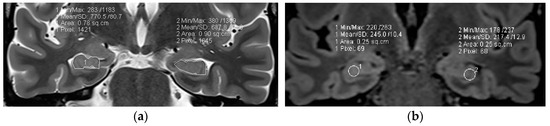

Coronal high resolution T2 weighted sequences and 3D Flair sequences are standard constituents of an epilepsy specific protocol to render visible hippocampal sclerosis, FCD type II, and areas of gliosis. Data postprocessing by MRI quantification relates to calculation of Flair and T2 signal (relaxometry) of the hippocampus and within lesions of the temporal lobe. Volumetry signifies quantification of the volume of the hippocampus and amygdala (Figure 7).

Figure 7.

MR volumetry (a) and T2/FLAIR relaxometry (b): right hippocampal abnormality histologically verified as hippocampal sclerosis and gliosis as evidenced by a mild area decrease of the right hippocampus (0.78 cm2 versus 0.90 cm2) and a slight FLAIR signal elevation (245 vs. 217). Both findings were suspected visually but were verified by postprocessing of volume and signal intensity.

In 78 patients with temporal lobe epilepsy, T2 relaxometry identified lesions in an additional 15 patients (19%) with visually normal MRI and volumetry identified a further 10 cases (13%) of hippocampal sclerosis. The combination of T2 relaxometry and volumetry provided the highest yield with recognition of hippocampal sclerosis in 22 (28%) patients with previous normal interpretations [81]. However, contrary to hippocampal sclerosis, FCD type I lesions, despite postprocessing, still have a high association with MR interpretation as “nonlesional”.